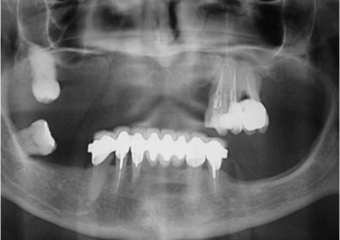

Raio X das próteses sobre implantes superiores e inferiores